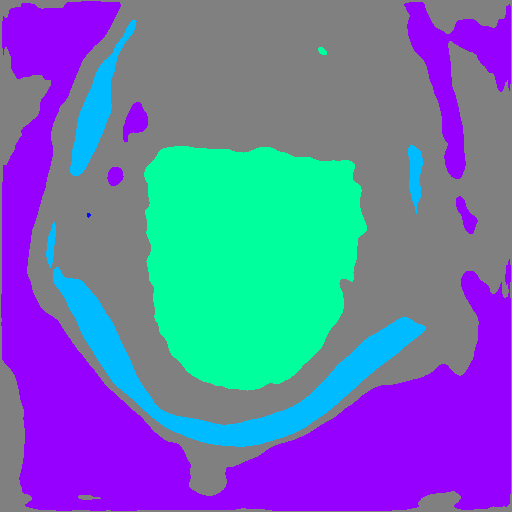

Refer to caption Refer to caption Refer to caption

Multi-class learning One-class positive-only learning (Ours) Multi-class positive-only learning

Figure 1: Decision boundaries of different learning settings. Colored markers represent positive data in different classes. “?” represents unlabelled data. Our proposed framework forms a multi-class positive-only learning setting which has distinct decision boundaries that aims to enclose positively labelled data for each class and can thus serve as an OOD detection mechanism based on non-enclosed areas.

3.2 Positive-only learning for multi-class segmentation

We start by illustrating the concept of positive-only learning. Figure 1 shows various decision boundaries with the presence of unlabelled data. Conventional multi-class classifiers show no ability to detect outliers within the unlabelled data. Instead, they categorise them into one of the known classes. Alternatively one-class classifiers can highlight outliers in the unlabelled data but they are limited to a single class. In contrast, our proposed method effectively identifies outliers in the unlabelled data while establishing distinct decision boundaries enclosing the labelled positive data for each class.